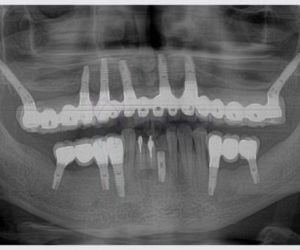

A evolução das técnicas de implantes dentários tem sido notável nos últimos anos, e uma das inovações mais significativas é o enxerto ósseo biomolecular. Este método revolucionário na medicina regenerativa proporciona uma integração mais eficaz entre o implante e o osso do paciente…